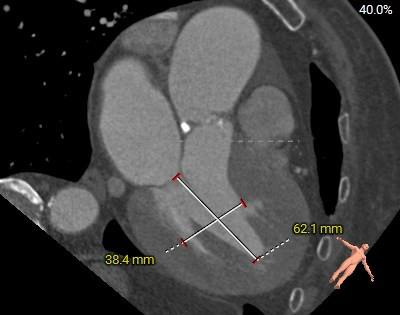

主动脉根部测量

◇ TYPE-0型二叶式主动脉瓣,左右冠不同窦,中重度钙化,钙化主要分布在瓣叶及交界区,左室流出道呈敞口状,综合多平面分析,预估瓣膜释放后有向下位移及瓣周漏可能;

◇ 左右冠高度可,左侧冠脉切线位瓣叶长度<左侧冠脉开口上缘到瓣叶附着缘距离长度<右侧冠脉开口上缘到瓣叶附着缘距离,左冠回旋支及右冠有钙化分布,结合瓦式窦及STJ预估冠脉阻挡风险较低;

◇ 左室心腔内径可;